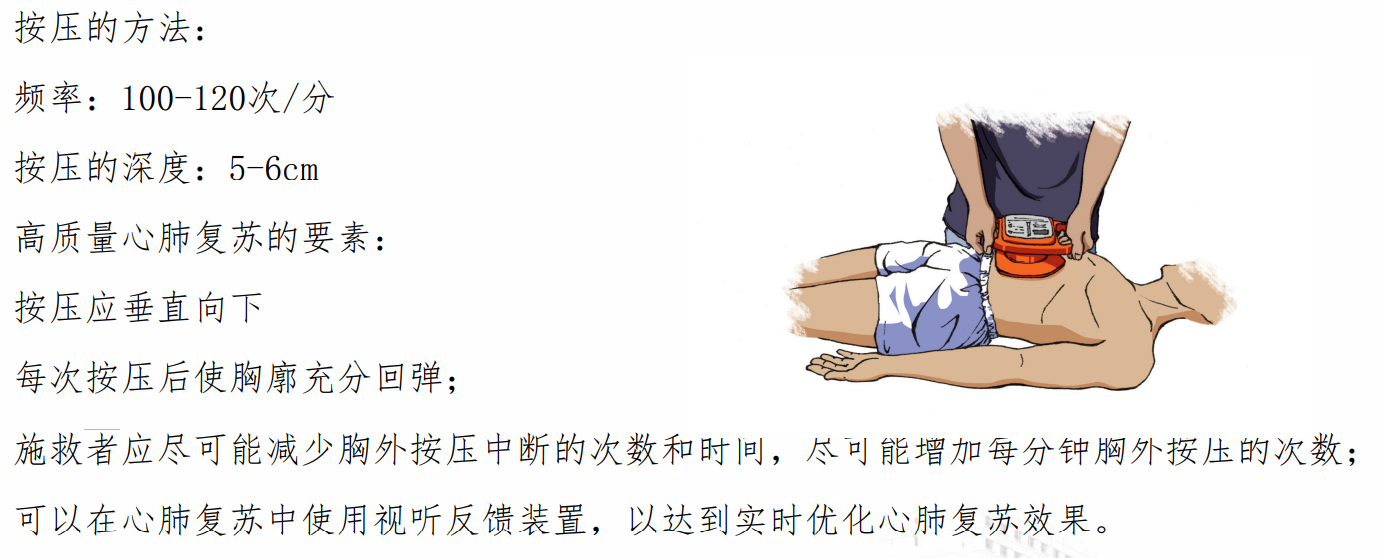

胸外按压:

按压的部位:胸骨中下 1/3 处

按压的方法:

按压总结: